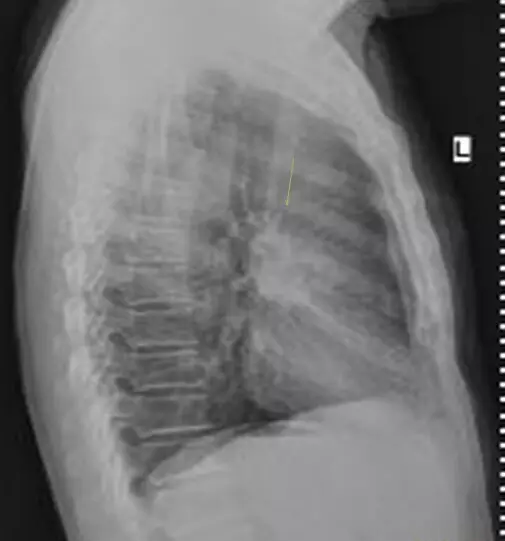

影像学所见:

胸部:气管分叉管壁增厚,右肺上叶前段软组织结节形成,考虑肿瘤性病变可能大。

影像诊断是非常重要的,因此我院专家组今日对肺癌影像诊断进行了讨论。专家组介绍到,在对胸部检查的同时,要着重检查胸部的正位和侧位,有些医院习惯性的只看正位而忽略了侧位,导致有些患者没有得到更准确的治疗。